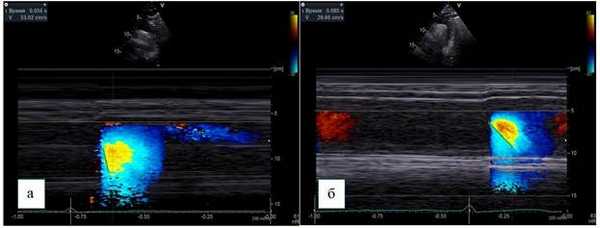

Комбинация М-режима и ЦДК представляет собой методику, которая используется для оценки «податливости» миокарда левого желудочка. При этом исследуются скорости распространения трансмитрального потока, которые характеризуют диастолическую функцию миокарда. Данную методику возможно использовать и в нисходящем отделе грудной аорты для оценки скорости распространения потока (СРП). В этом случае методика будет отражать упруго-эластические свойства стенок грудной аорты [14]

Курсор М-режима располагается параллельно потоку нисходящего отдела грудной аорты, и в сочетании с цветовым доплеровским картированием производится запись цветовой волны потока, получаемой с помощью элайзинг-эффекта, который достигается путем установки предела Найквиста 30-70 см/c.

Скорость распространения потока в цветовом М-режиме определяется как отношение расстояния между точками, отображающими начало и конец наклона цветовой волны потока, ко времени между двумя этими точками (рис. 3).

Рис. 3. Супрастернальная позиция, М-ЦДК нисходящего отдела грудной аорты.

Способ определения СРП:

а - пациент без коронарного атеросклероза, СРП - 530 мм/с,

б - пациент с коронарным атеросклерозом, СРП - 296 мм/c